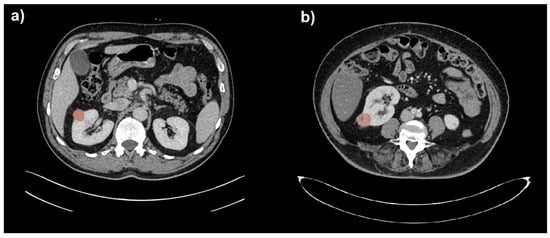

The CT images and related radiological data were extrapolated from the PACS data archiving system of Parma University Hospital. Images were anonymized before their export. Two readers (R1, a radiologist with 15 years of experience in abdominal imaging; R2, a radiologist with 3 years of experience in abdominal imaging) reviewed the CT scans (blinded to clinical and pathological information). The abdominal CTs of the patients included in the study were then imported into 3D Slicer software version 4.10.2 [24]. The radiologist with 3 years of experience (R2) manually delineated the region of interest (ROI) along the edge of the lesion, layer by layer, on the portal venous phase by manually drawing the tumor boundaries. The ROI was used to delineate the boundary of all planes of the renal mass, including necrosis, cystic degeneration and hemorrhage; however, it did not include normal renal tissue or perirenal fat. The volume of interest (VOI) of the lesion was then automatically generated by the software. Finally, another senior radiologist (R1) examined the outlined results on multiplanar reconstruction (MPR) images. Examples of benign and malignant small renal masses with respective segmentations are depicted in Figure 1. No image preprocessing such as wavelet and LoG transformations was performed on CT images before radiomic analysis, so only RFs belonging to the original type were considered. Subsequently, 108 RFs were extracted from the VOI using the SlicerRadiomics® tool [25]. The extracted RFs included both first-order and subsequent-order features, including shape, first-order, Gray-Level-Co-occurrence-Matrix (GLCM), Gray-Level-Run-Length-Matrix (GLRLM), Gray-Level-Size—Zone-Matrix (GLSZM), Neighboring-Gray-Tone-Difference-Matrix (NGTDM) and Gray-Level-Dependence-Matrix (GLDM) functions.

Figure 1. Segmentation (in red) of a benign (a) and a malignant (b) small renal mass (SRM) hardly distinguishable on portal venous phase CT images.